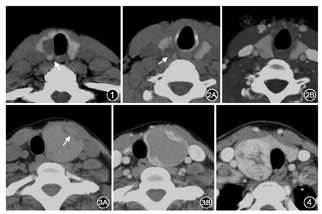

统计显示,结节形态不规则、咬饼征、微钙化、增强后缩小/模糊更常见于MN中(图1,图2),而囊变为主和高强化征象更常见于BN中(图3,图4)(表1,表2)。结节形态不规则、咬饼征、微钙化、增强后缩小/模糊诊断MN的敏感度和特异度分别为80.5%和90.0%、74.2%和94.3%、35.6%和90.1%、80.7%和79.4%;囊变为主和高强化对BN诊断的敏感度和特异度分别为42.2%和98.1%、19.0%和97.4%。

甲状腺BN多呈膨胀性生长,其边界多为规则的圆形、椭圆形或甲状腺塑形,而MN多呈浸润性生长,其边界多不规则,本组单因素和多因素分析均显示形态不规则更常见于MN中,比值比(OR)值为5.297,接近超声形态不规则OR低位值(2.7~37.788)[9,10],其诊断MN的敏感度(80.5%)和特异度(90.0%)均较高。咬饼征对甲状腺癌的诊断价值已得到部分学者的认可[2],其组织学基础为瘤体累及或接近甲状腺被膜,本组单因素和多因素分析均显示咬饼征更常见于MN中,OR值为3.467,与形态不规则比较,其诊断MN的敏感度(74.2%)虽较低,但特异度(94.3%)增高。

微钙化对甲状腺MN的诊断价值已得到广泛认可,尤其是乳头状癌[4,5,6,7,8,9,11],其主要病理基础是砂粒体,本组单因素和多因素分析虽显示微钙化更常见于MN中,但OR值仅1.730,明显低于超声微钙化(3.115~9.9)[12,13],考虑与CT软组织分辨率低而易遗漏微钙化有关,微钙化诊断MN的特异度虽较高(90.1%),但敏感度低(35.6%),故不宜单独应用。结节性甲状腺肿是甲状腺最常见的BN,结节周边可有程度不等的纤维化,进而影响血供,导致结节出血、坏死、囊变;而以乳头状癌为主的MN,其间质丰富,生长缓慢,虽较大瘤体亦可囊变,但仅3%的瘤体囊变超过50%[8],本组囊性为主更常见于BN中,虽敏感度(42.2%)较低,但OR值(7.537)和特异度(98.1%)高。

乳头状癌等MN和小滤泡为主的腺瘤样结节梗死及玻璃样变性等较少,增强后明显强化,与甲状腺间密度差降低,瘤体低密度区缩小/模糊,部分甚至高于甲状腺而呈高强化;结节性甲状腺肿富含纤维、梗死及玻璃样变性等,这些成分强化较低或不强化,与甲状腺间密度差增大,瘤体低密度区转清晰。本组增强后范围缩小/模糊更常见于MN中,OR值为5.729,高于形态不规则、咬饼征和微钙化,但其特异度较低(79.4%),提示该征象亦不宜单独应用。尽管高强化对BN的敏感度较低(19.0%),但特异度(97.4%)和OR值(10.782)均较高,说明高强化仍不失为诊断BN的重要征象。